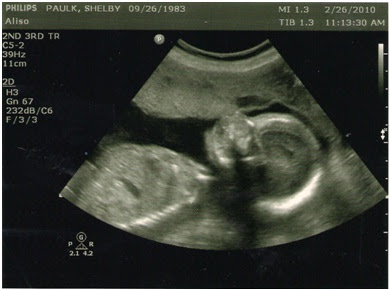

We had our 20 week utrasound yesterday and finally found out that our third baby is a GIRL! We’re so excited and I think Riley was even more excited, she can’t wait to have a baby sister to “play dress up with” as she’s said. The baby looks great and is measuring right at 20 weeks. I absolutely love having ultrasounds because it gives us a peak at our little one. We almost weren’t able to see whether she was a she or he because she had her hands, this time, between her legs, but thankfully by the end she moved them. I told Ty we need to start thinking of names now because we’re really bad at agreeing on baby names. Hopefully we can start soon and have something before she’s born!

Ty is still not 100 percent convinced we’re actually having a girl. I have to admit, the u/s tech was having difficulty getting a good shot because of the baby’s hands being in the way, but I’m fairly confident she’s a girl…guess we’ll find out for sure in 4.5 months. Enjoy a few pictures of our newest!

Baby’s face

Update: I had my doctor appointment and I was 20 weeks, 4 days. Baby looks great; her heart beat was at 162. My BP was 96/62 and I weighed 118 (started this pregnancy at 108). So far I’ve gained 10 lbs. I feel great right now and hope it continues! Baby is moving a ton, I can’t tell when she moves the most because her movement is almost constant. However, I can always feel her when I lay on my back. She seems to always lay and kick on my right side.